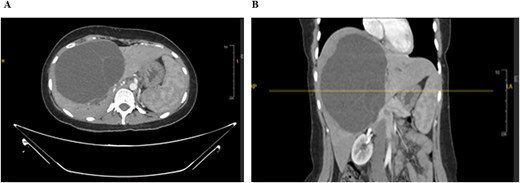

Laboratory studies were performed for serum alpha-fetoprotein (AFP), carcinoembryonic antigen (CEA), and carbohydrate antigen (CA). All the above investigations were normal except for an elevated level of CA-19.9. A computed tomography (CT) of the abdomen and chest with an intravenous contrast scan was performed. Chest imaging did not reveal any malignancy. Abdominal imaging demonstrated a big, multiseptated hepatic cystic mass, measuring 14 × 11 × 16 cm, involving segments 4A, 4B, 5, 6, and 8, shown in Fig. 1.

CT scan of the abdomen: Demonstrating the hepatic mass measuring involving the segments 4A, 4B, 5, 6, and 8. A) Transverse view, B) longitudinal view.

The mass had fine, minimally enhancing septations without any solid enhancing component. Communication with the right intrahepatic biliary ducts was observed, leading to moderate intrahepatic biliary duct dilatation. Magnetic resonance imaging (MRI) of the liver using contrast reveals a large hepatic cystic mass, corresponding to dimensions noted on CT, showing bright T2 signal intensity with thin septations without a solid component, illustrated in Fig. 2.